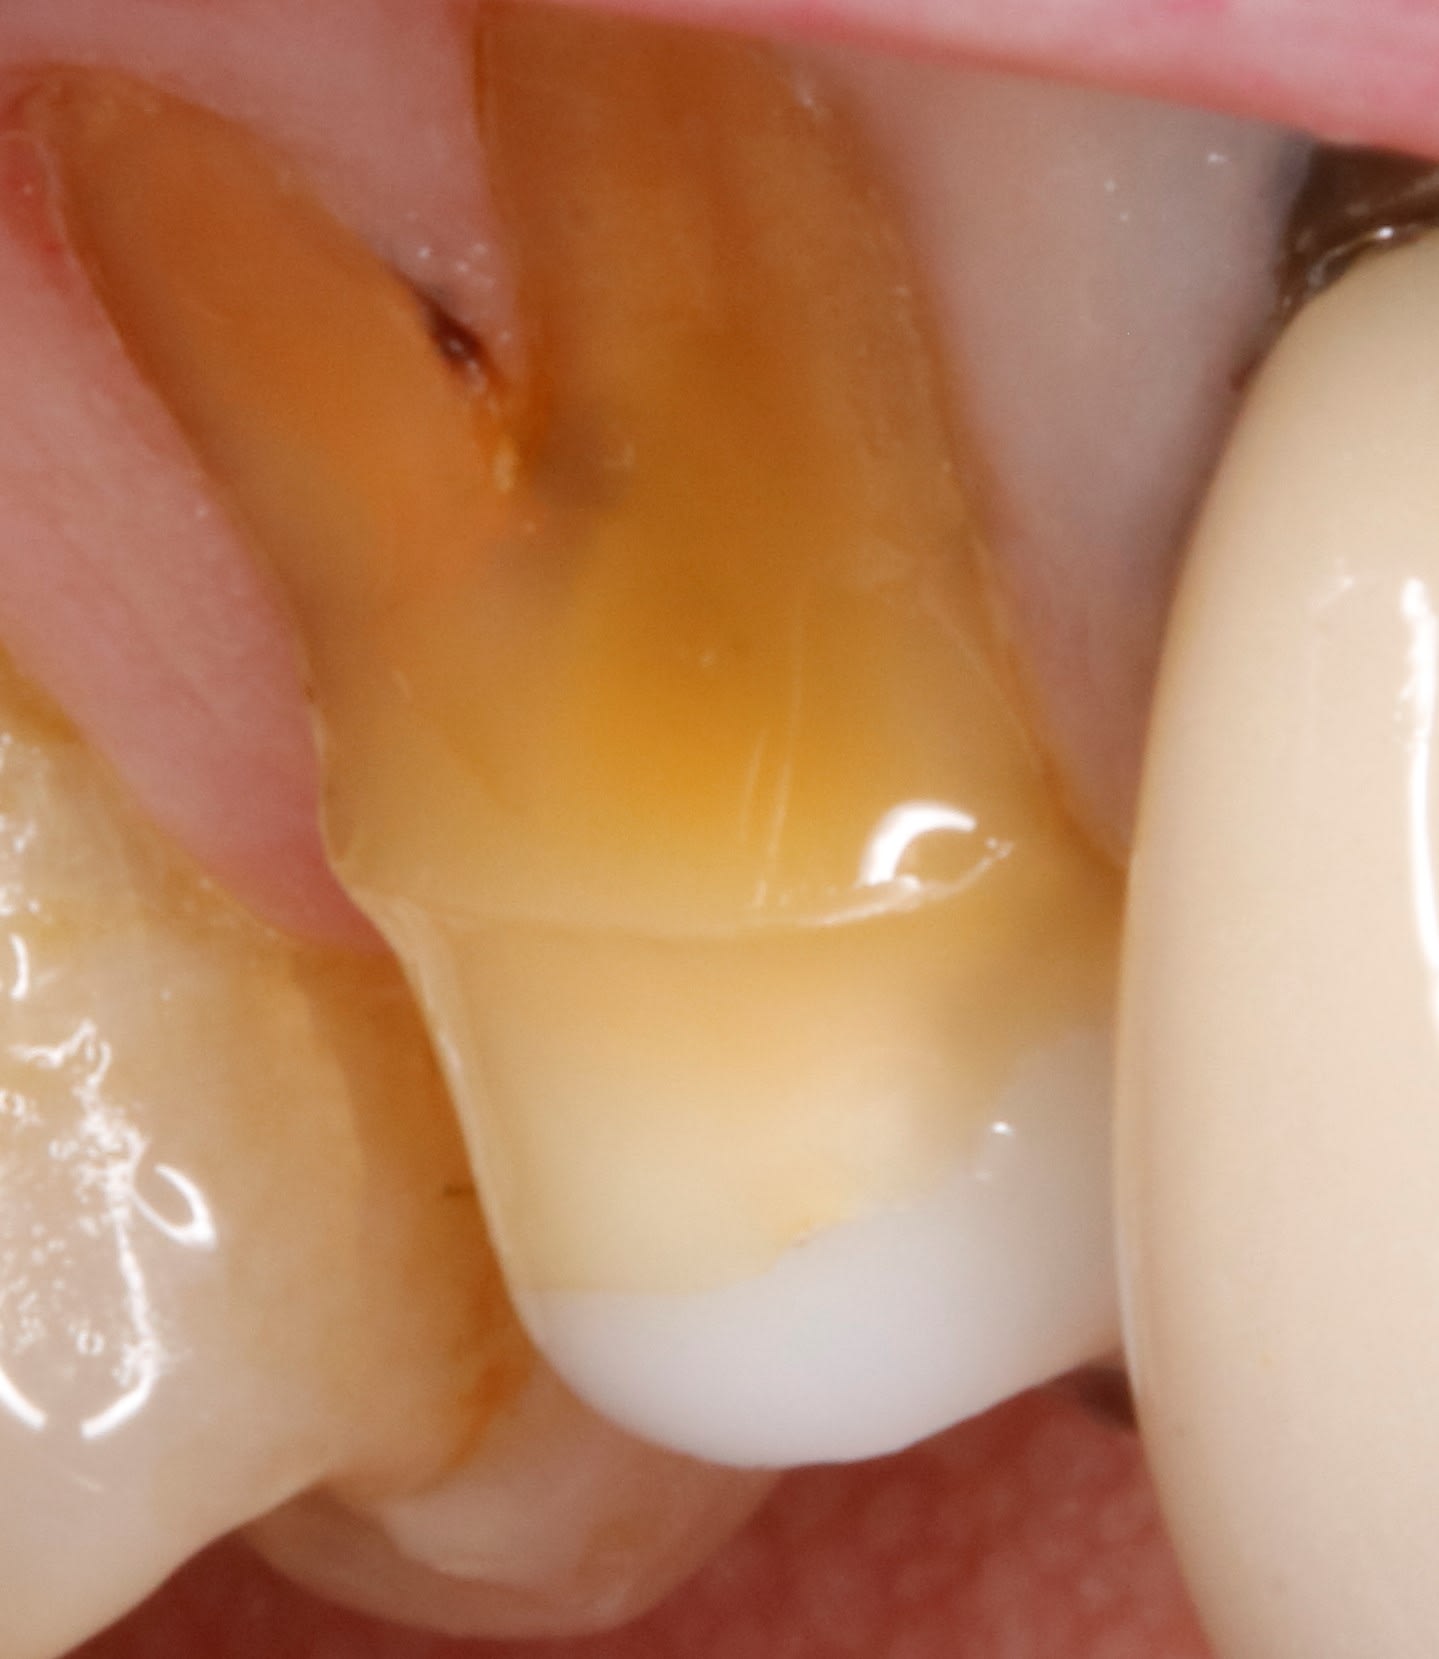

bon , comme vous étés gentils , voilà les tailles faites à l instant .

- ensuite , le fait d avoir fait la pre-taille la fois d avant , et de l avoir laissé sans prov , aujourd'hui j ai pu descendre en infra sans une goutte de sang .

du coup regardes la gencive comme elle est belle . on voit meme que la dent s est teinté , alors zou

un petit coup de bossette avec detartrine et hop un pt'it mordu sans fil sans produit sans rien.

et la fois d apres la couronne rentre impec dans le sulcus comme un doigt au cul :-)

donc aujourd’hui , , tjs sans prov , la gencive est impec .

y a plus qu a mettre .

Eh oui la gencive est belle quand on laisse la nature tranquille. Good job